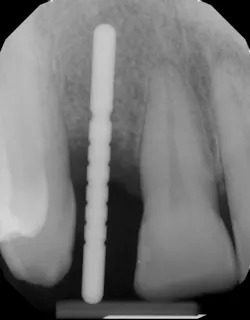

A quick clinical intervention to rectify incorrect initial osteotomy preparation can be accomplished with a Lindemann bur. A Lindemann bur is a side-cutting bur used to move pilot preparation in a bodily manner with ease and without the likelihood of further angulation issues (figure 4). After initial pilot drilling, a radiographic locator is placed to check position. If the radiographic index is shown to be incorrect, under copious irrigation, place a Lindemann bur in the osteotomy parallel to the intended location and move in a rigid upright fashion to the ideal location. Take a radiograph to verify correct position.